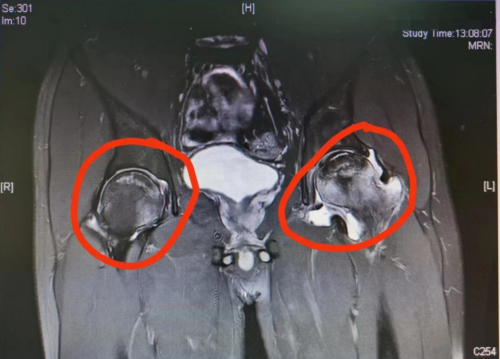

标记处为股骨头坏死磁共振下表现

股骨头坏死又称股骨头无菌性坏死,或股骨头缺血性坏死,是骨坏死的一种。股骨头局部血运不良,引发股骨头血液循环障碍,从而使得股骨头进一步缺血、坏死、骨小梁断裂、股骨头塌陷的一种病变。